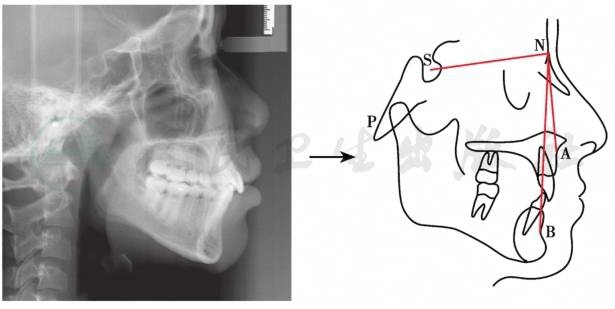

四、X线头影测量分析

X线头影测量分析用于正颌外科的目的在于协助诊断,明确畸形的特征,并用测量分析所取得资料进行治疗设计,疗效预测和评价。X线头影测量主要是侧位定位片的分析,这里仅介绍最常用来分析上下颌骨及其与颅底位置关系的三个测量项目:SNA角、SNB角和ANB角。

(一)测量标志点(图4)

1.蝶鞍点(S)。

2.鼻根点(N)。

3.上牙槽座点(A)。

4.下牙槽座点(B)。

图4头颅侧位片及常用测量标志点与项目

引自:口腔颌面外科学(第8版).第1版.ISBN:978-7-117-29388-4.主编:

(二)测量项目(图4)

1.SNA角

S-N连线与N-A连线形成的交角代表上颌骨位置。正常值为82°±2°。

2.SNB角

S-N连线与N-B连线形成的交角代表下颌骨位置。正常值为78°±2°。

3.ANB角

SNA角减去SNB角的值代表上下颌骨相对位置。正常值为4°±2°。